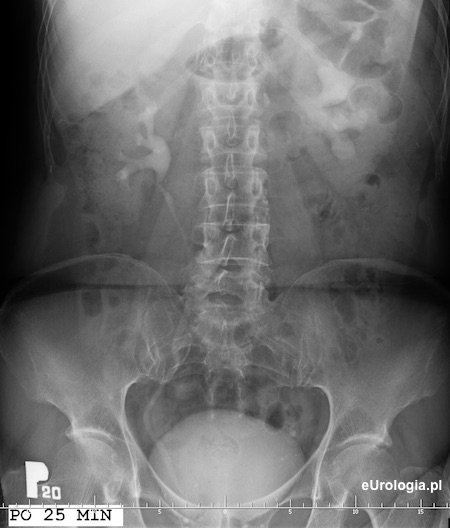

Po 25 minutach zakontrastowaniu ulega wodonerczowato poszerzony układ zbiorczy lewej nerki

Wodonerczowato poszerzony układ zbiorczy lewej nerki. Poszerzenie moczowodu lewego aż do opisywanego cienia w miednicy małej - złóg w dolnym odcinku lewego moczowodu.